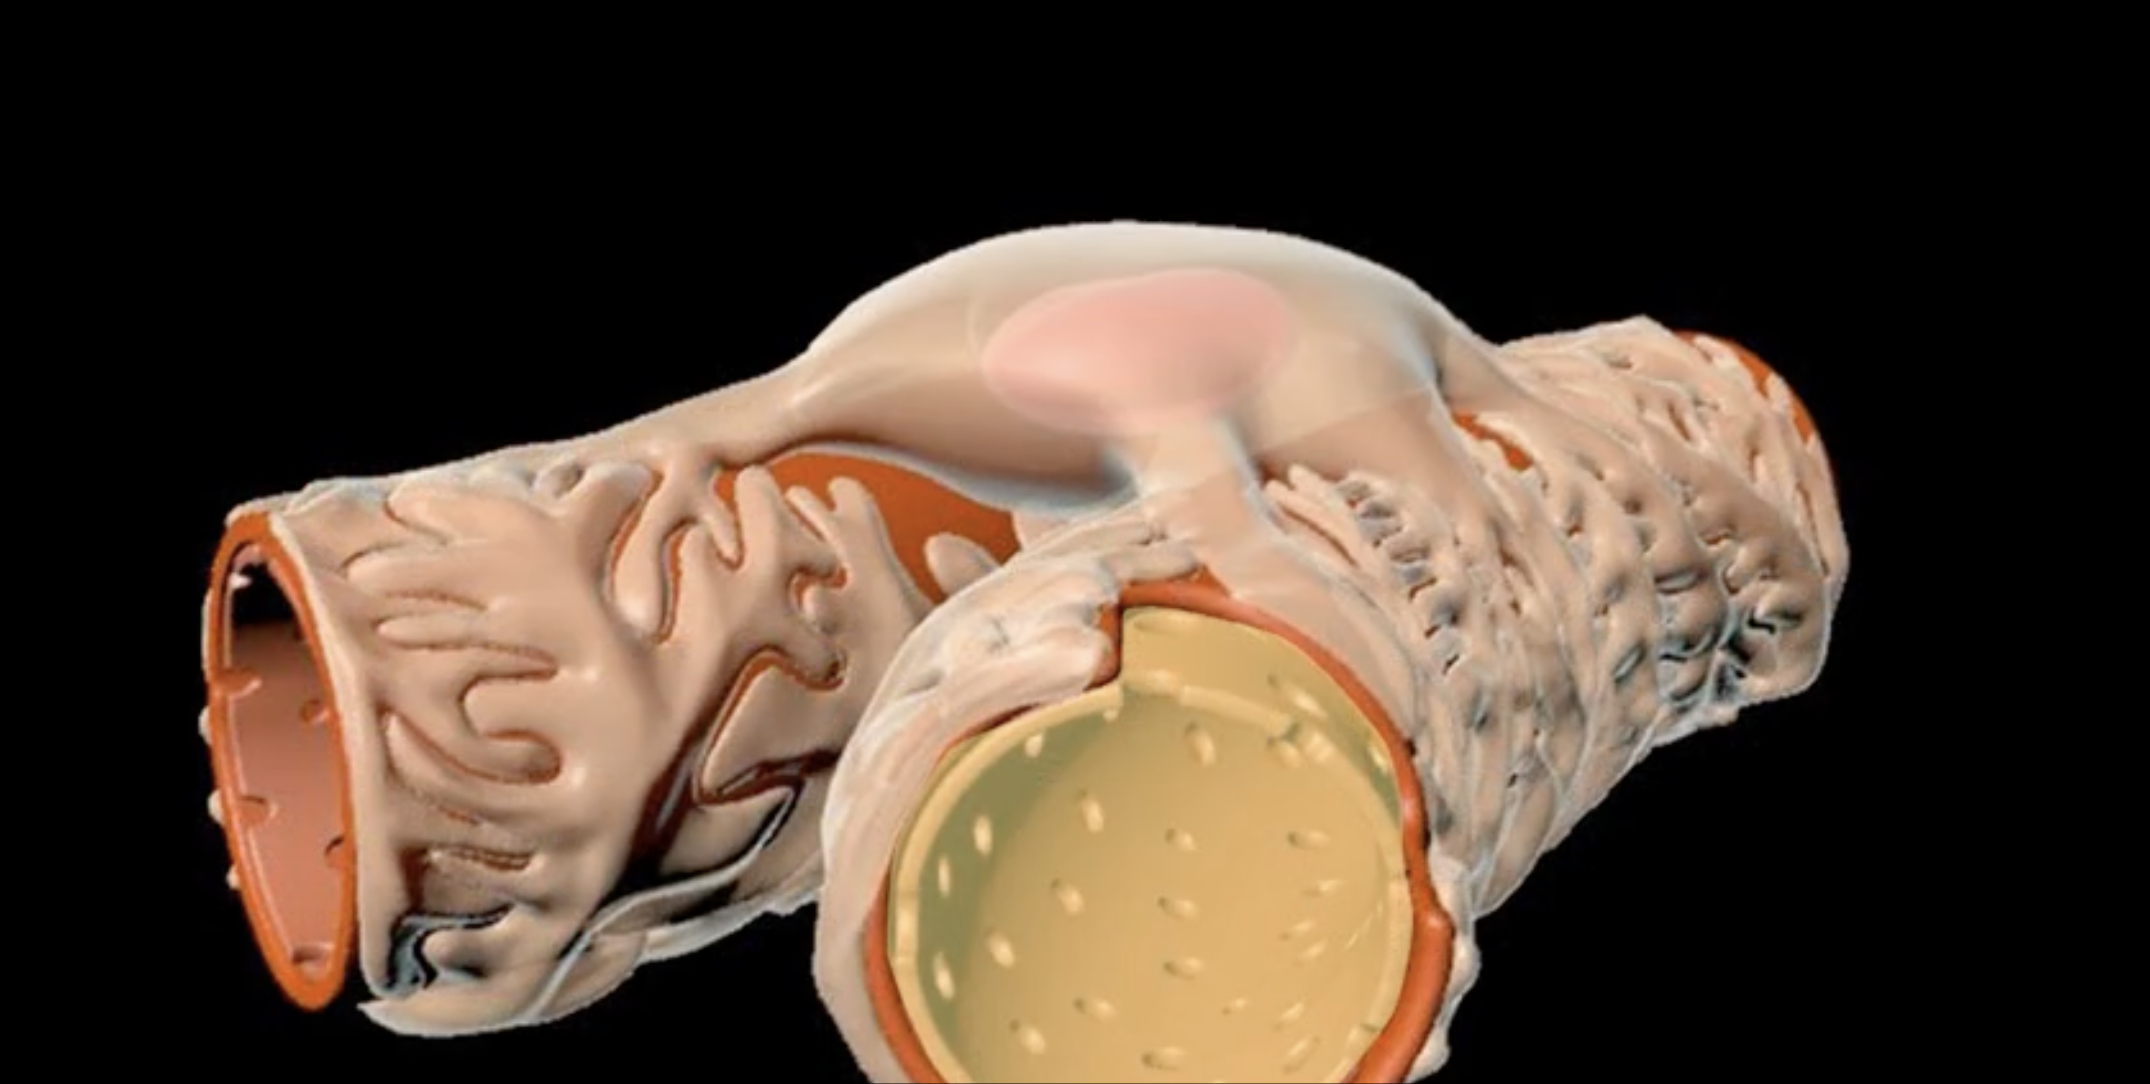

renal cortex

green

renal medulla

blue

renal columns

yellow

renal pyramids

purple

renal lobe

orange

renal papilla

minor calyx

teal

major calyces

renal pelvis

minor and major calyces